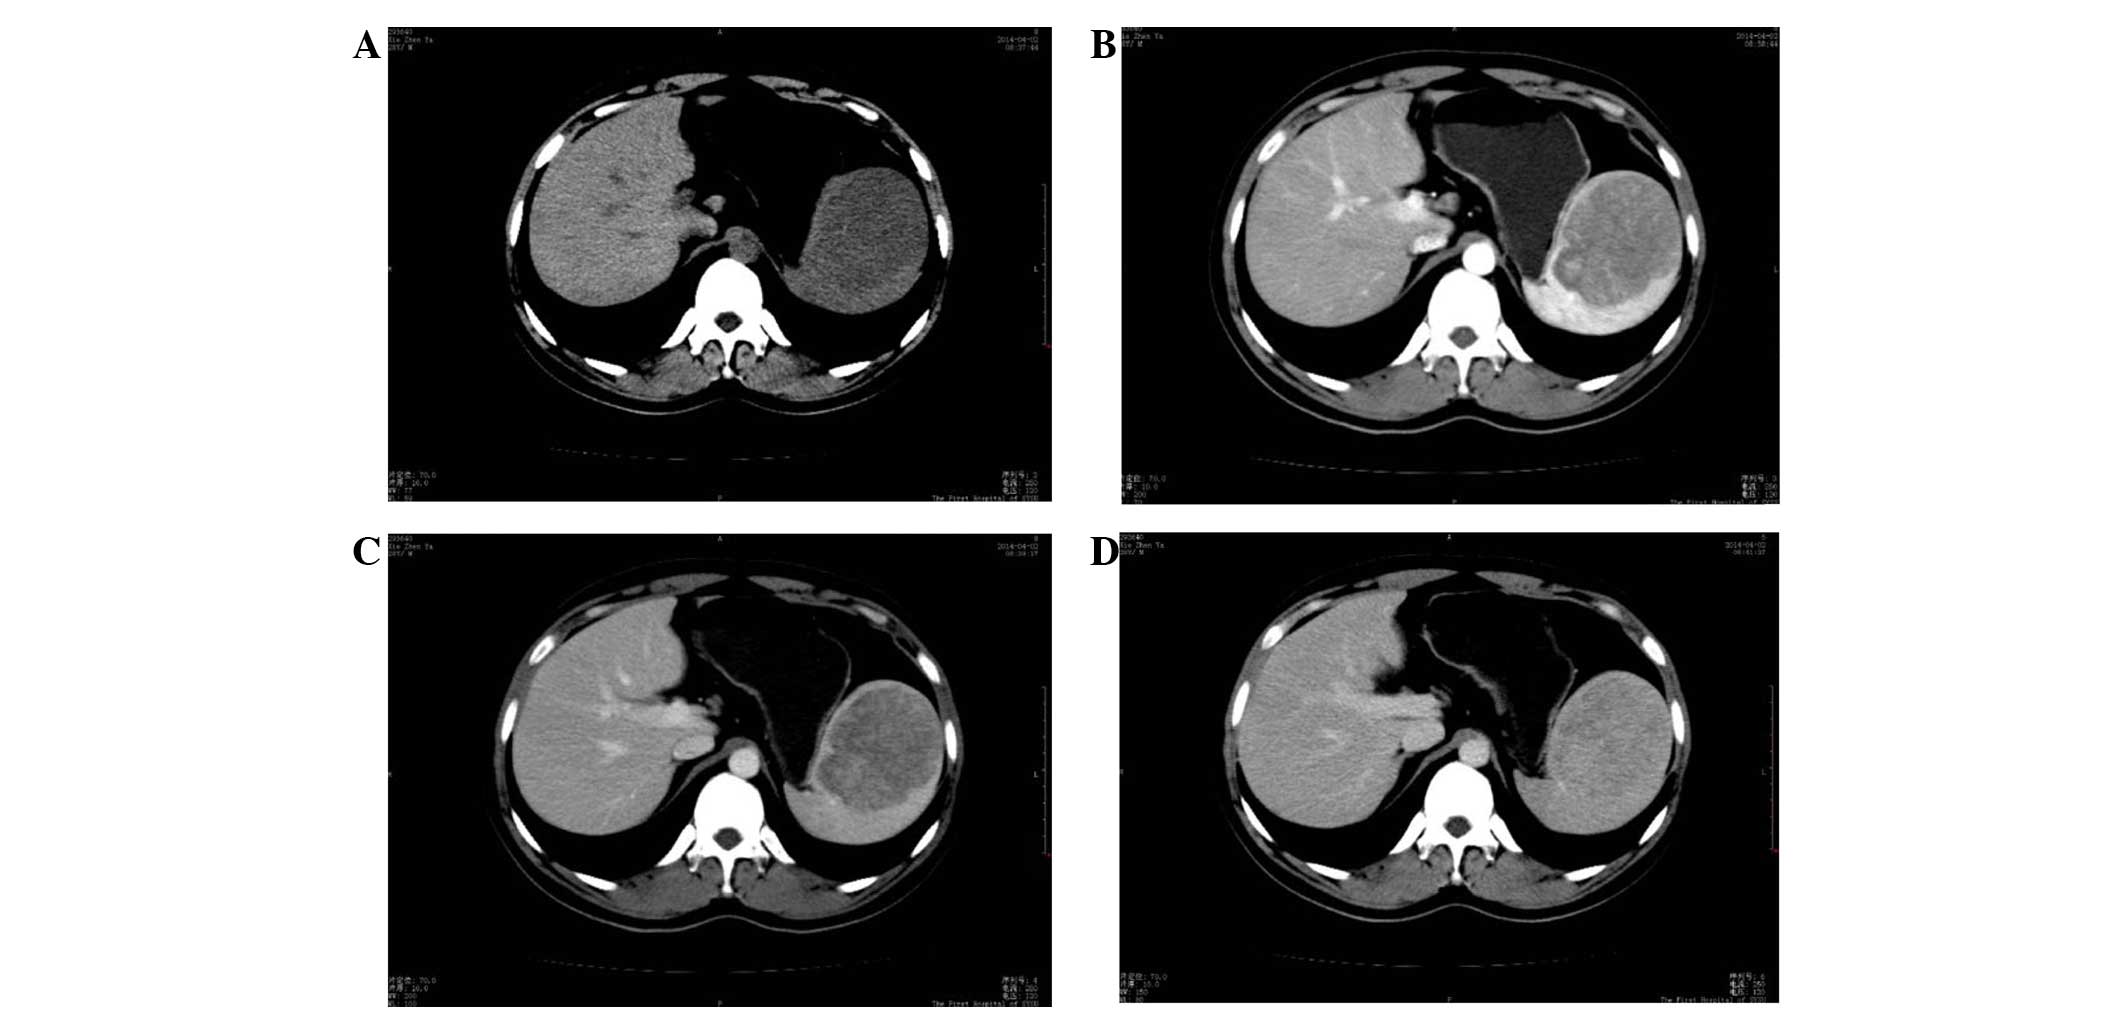

A 29-year-old man presented to the Department of Surgery, The First Affiliated Hospital, Sun Yat-sen University (Guangzhou, China) on March 30, 2014 with a 1-year history of left upper quadrant and back discomfort. The discomfort was intermittent, but had become progressively worse since it first occurred. There was no history of fever, weight loss and other medical issues, and the patient's respiratory, digestive and urinary systems were normal. Abdominal examination found no positive physical signs. Hematological parameters, and liver and kidney function tests were unremarkable. On computed tomography (CT) scan, a round mass of 76×74 mm was observed in the spleen, which showed slightly low density on a plain scanning CT image (Fig. 1A). CT values of the mass and the surrounding normal splenic tissue were ~40 and 42 HU, respectively, prior to the injection of contrast medium. The mass showed heterogeneous moderate enhancement with a value of 66 HU, which was clearly lower than that of the surrounding normal spleen (136 HU) on arterial phase-enhanced CT scanning. Certain regions within the lesion were significantly enhanced (Fig. 1B). The CT value of the mass was slightly increased (80 HU) on portal venous phase-enhanced CT scanning, but remained lower than that of the surrounding spleen (116 HU) (Fig. 1C). The densities of the mass and the normal surrounding spleen were close on delayed enhanced CT scanning after a delay of 3 min (Fig. 1D). The patient underwent a splenectomy. A well-circumscribed mass measuring 7 cm in diameter was noted in the cross-sections of the resected specimen. On gross examination, the mass exhibited a gray-white or gray-red cut surface with fibrous septa traversing throughout and was divided into discrete complete or incomplete nodules.

Figure 1.

CT scans of sclerosing angiomatoid nodular transformation. (A) Slightly low density lesion on a plain scanning CT image. (B) The CT value of the mass was clearly lower than that of the surrounding normal spleen on arterial phase-enhanced CT scanning. (C) The CT value of the mass remained lower than that of the surrounding spleen on portal venous-phase enhanced CT scanning. (D) The densities of the mass and the normal surrounding spleen were close on delayed enhanced CT scanning (D). CT, computed tomography.